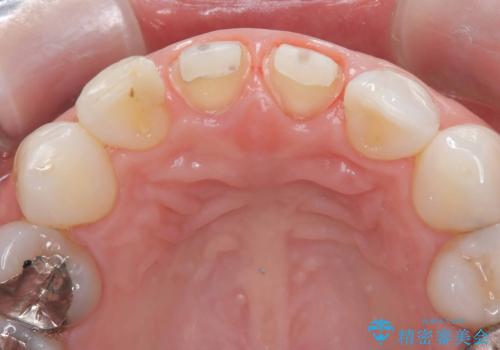

- [前歯の色が気になる」を主訴に来院された患者様です。歯の形を整えた後オールセラミッククラウンで治療を行いました。

以前他院にてセラミッククラウンを被せていたのですが、セメントの劣化なのか色が青白くなっていました。

歯の形を整えた後、色が透けないよう処置をしてオールセラミッククラウンで治療を行いました。